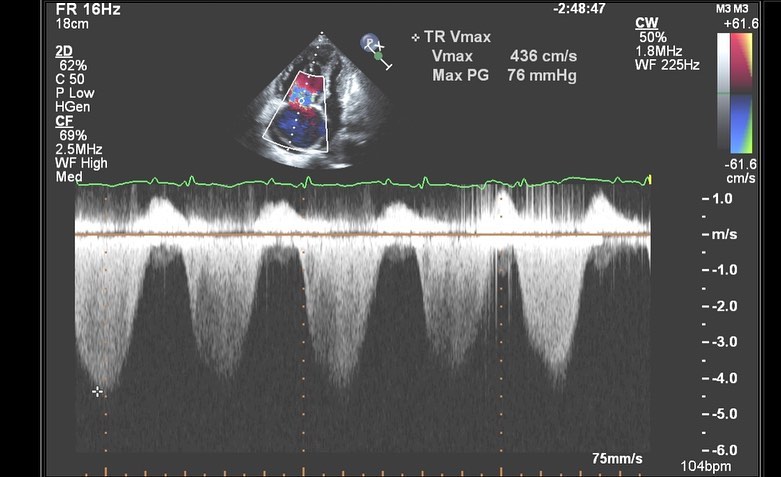

📷6️⃣: CW Doppler shows a thick dense TR jet. The estimated PA systolic pressure is markedly elevated. Adding on an RA pressure of 15, which this individual had, yields a PA systolic pressure of nearly 90 mmHg.